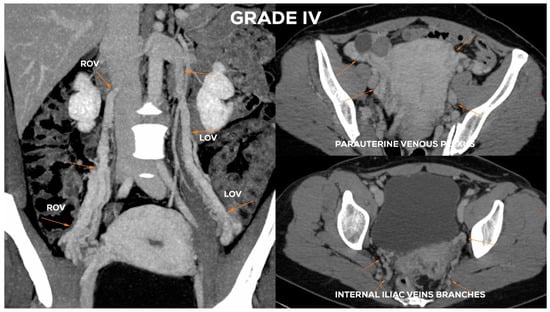

4.2.6. Grade IV (GIV)

| øLOV | incLOV | lPUV | bLIILV | øROV | incROV | rPUV | bRIILV | |

|---|---|---|---|---|---|---|---|---|

| GI | <6 | (−/+) | <5 | <5 | <5 | (−) | <5 | <5 |

| GI/II | 6–6.5 | (+) | <5.5 | <5.5 | <5 | (−) | <5 | <5 |

| GII | <7 | (+) | <6.5 | <6 | <5.5 | (−) | <5.5 | <5.5 |

| GII/III | 7.5–8 | (++) | <7 | <7 | <6 | (−/+) | <6.5 | <6 |

| GIII | >8 | (++) | 7–8 | <7.5 | <7.5 | (+/++) | <7 | <6.5 |

| GIV | >10 | (+++) | >8 | >8 | >8 | (+++) | >7.5 | >7 |